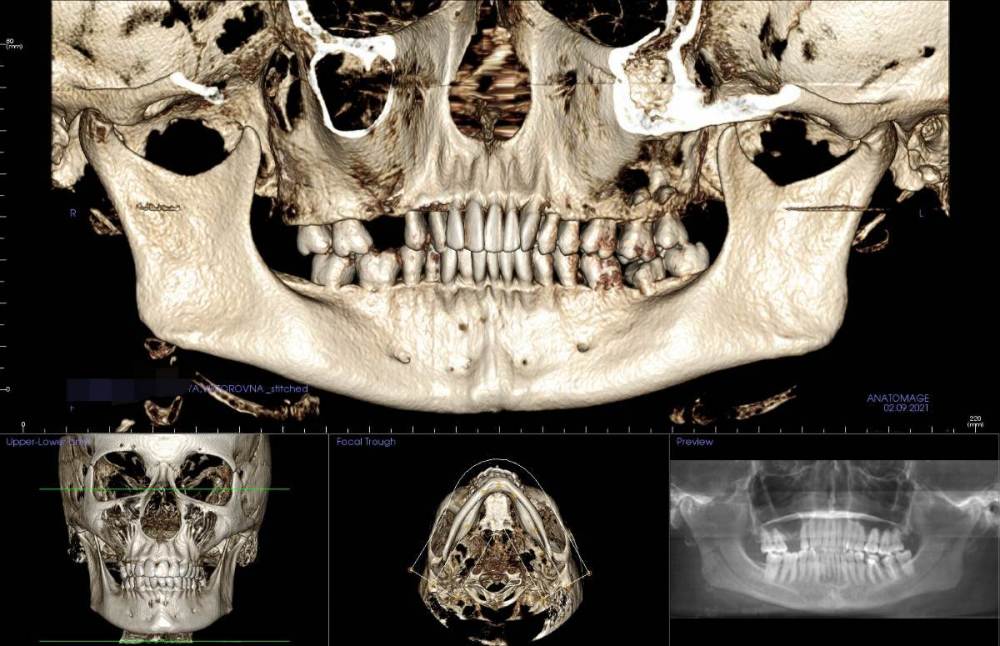

Ситуация в следующем: у меня стоят брекеты, пока только на верхней челюсти, ношу ~8 мес. На нижней челюсти в переднем отделе обнаружена цементно-костная дисплазия. Делалось два КТ, первое в 2021 (перед установкой верхней челюсти), второе месяц назад для оценки динамики перед установкой брекетов на низ. Дисплазия стала немного больше, но выглядит лучше (больше костной ткани).

Вопрос: можно ли ставить брекеты на нижнюю челюсть при таком диагнозе? Какие есть риски, осложнения? На фото КТ, сделанное в 2021